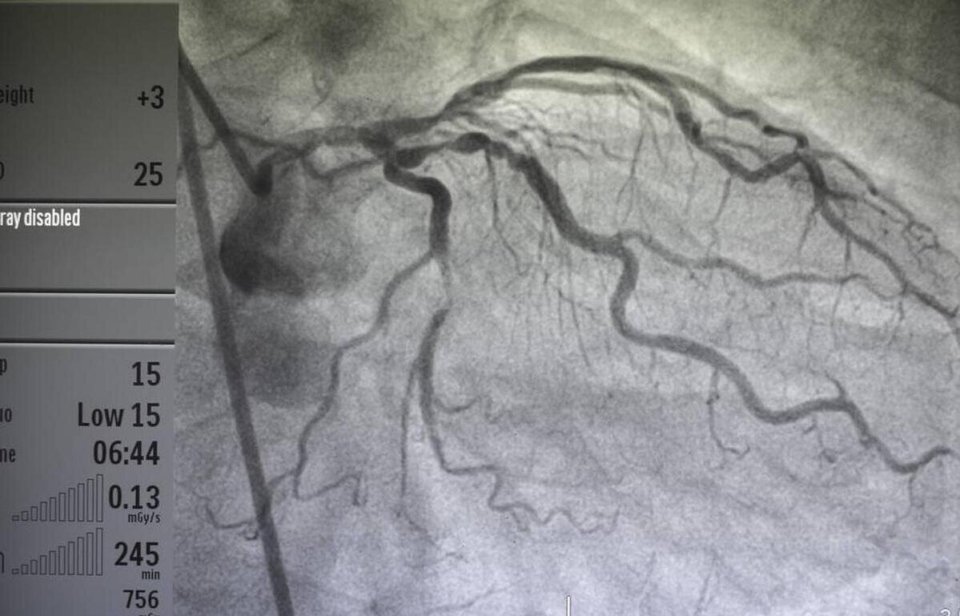

如果高度怀疑是冠心病,以上的检查都无法确诊,需要进行冠脉造影,这是冠心病诊断的“金标准”。没有前面的检查评估,也就无法进行进一步的冠脉造影检查。对于前面的检查考虑冠心病可能性较小的人,冠脉造影可能就不需要进行,毕竟这是微创检查,有一定的风险。

图片

总之,冠心病等心血管病的诊断要根据临床的表现,体征,相关的检查来明确。心脏就像我们“四室”的房子,要想看看电路通不通,有没有短路或者断路,那就检查心电图;如果想了解房间的水管通不通,那就查冠脉造影;如果想搞清楚房间结构大小以及房门开合是否正常,那就只能靠心脏超声了。#世界心脏日#